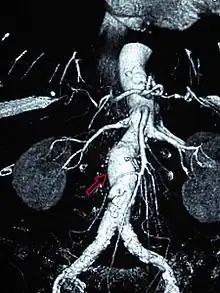

A ruptured AAA with an open arrow marking the aneurysm and the closed arrow marking the free blood in the abdomen -

Sagittal CT image of an AAA